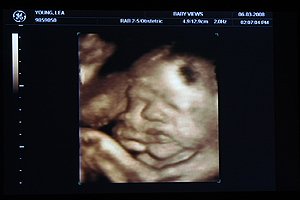

Roll out the red carpet for your baby. A 4-D ultrasound of Lea Youngs baby is seen at Baby Views in Little Rock. Where we are located.

Green Day Last Night on Earth. The three-dimensional images in a 4-D ultrasound are rendered with the same sound waves as a 2-D ultrasound as Kate. North Little Rock Womens Clinic - 3401 Springhill Dr Suite 390 North Little Rock AR 72117.

Josephs Helpers in Little Rock has received a new ultrasound machine costing just under 30000. The 4D ultrasound captures real-time movement of the baby using safe sound-wave technology. For many parents welcoming a healthy newborn into the world is a joyous occasion but it can also be stressful when.